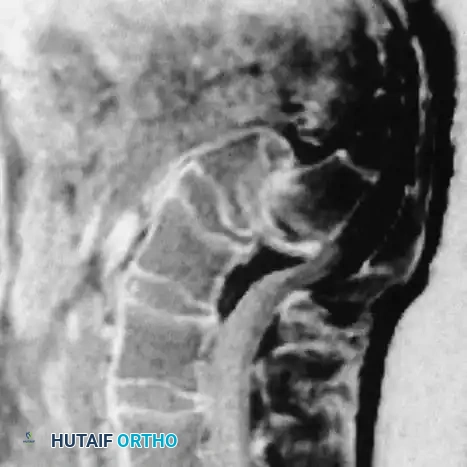

Furthermore, the competency of the intervertebral disc at the affected level plays a vital role in resisting shear. Early disc degeneration or failure exacerbates instability. Magnetic Resonance Imaging (MRI) is often required to accurately assess disc hydration and structural integrity.

- Magnetic Resonance Imaging (MRI): Essential for evaluating disc hydration, central canal stenosis, and foraminal compromise affecting the L5 nerve root.

Boxall et al. established that angular relationships (sagittal rotation or slip angle) are superior predictors of instability and progression compared to simple translational percentage. A high slip angle indicates severe localized lumbosacral kyphosis.